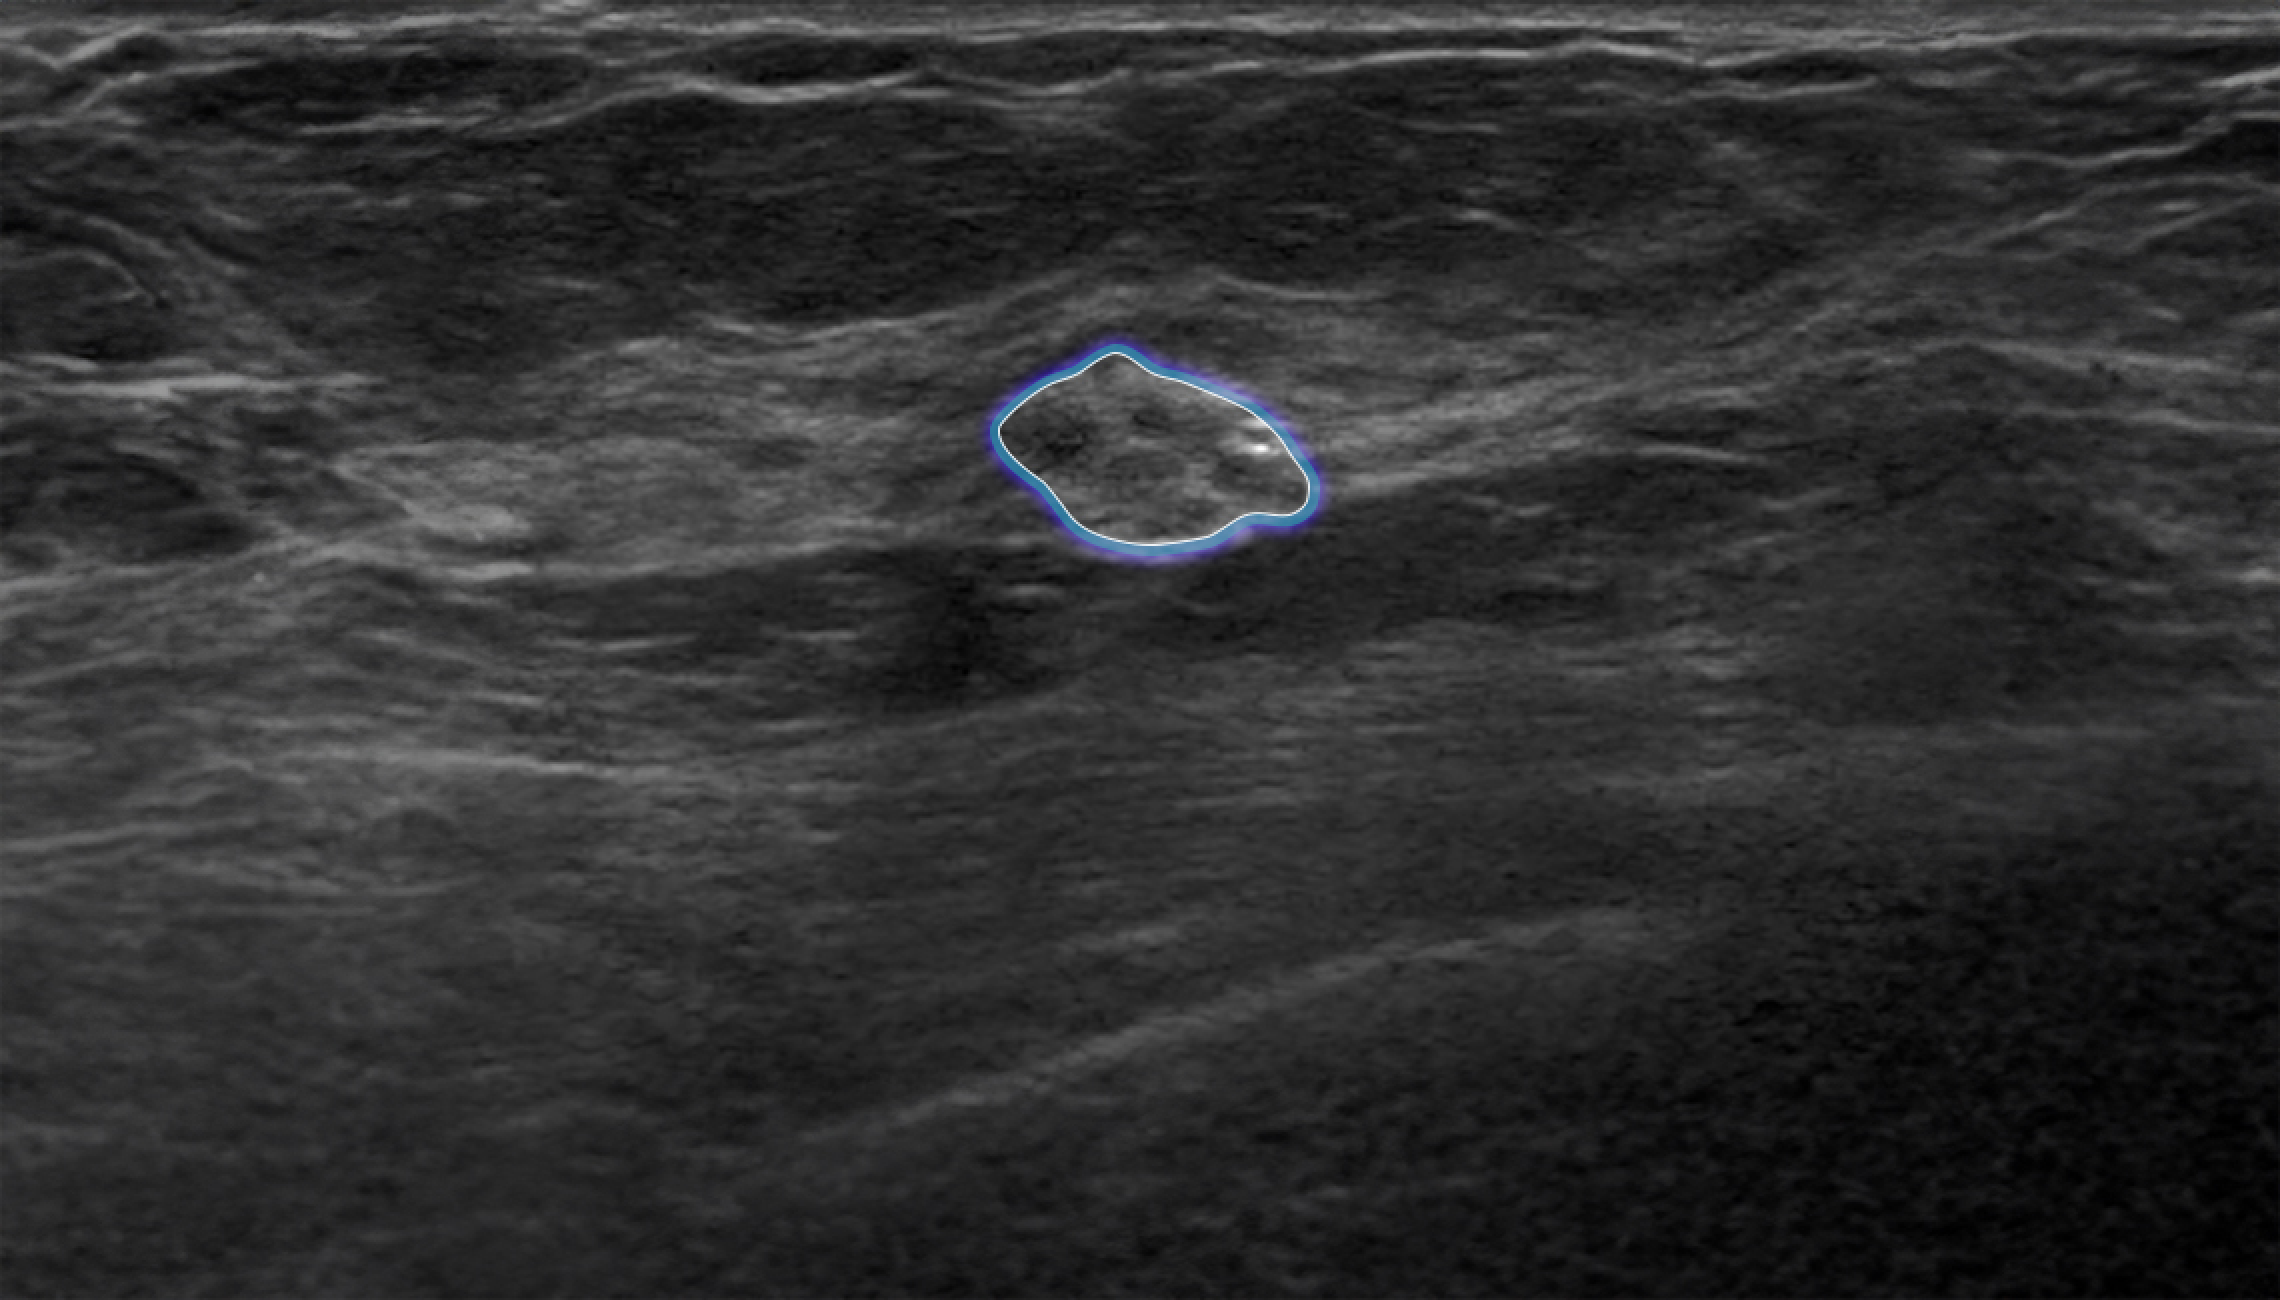

Follow up mode

Automatically matches lesions from previous breast ultrasound examinations, allowing for easy comparison of changes in the lesions.